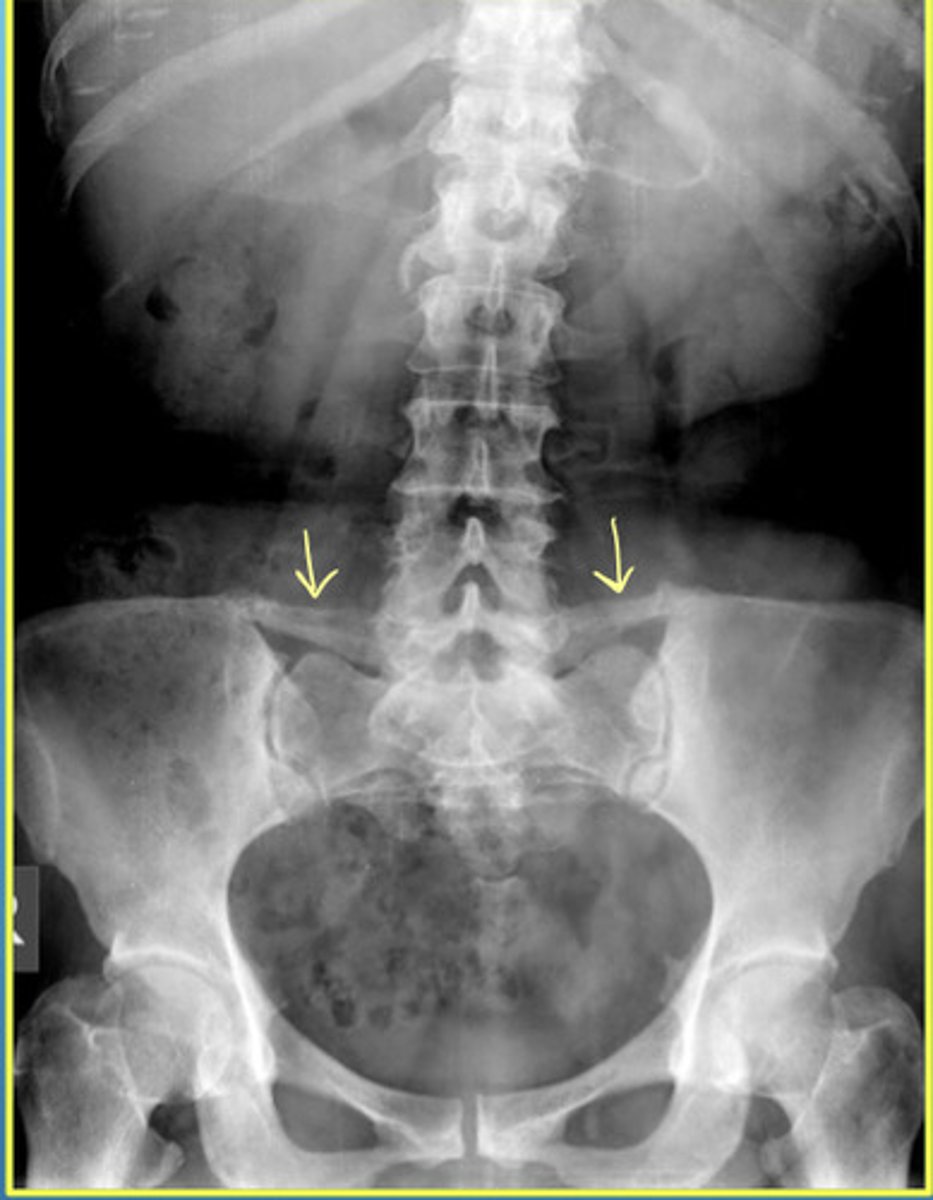

Iliolumbar Ligament Calcification

Iliolumbar Ligament Calcification AND a Transitional Segment